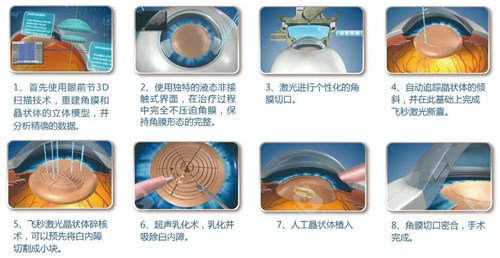

医疗服务不仅包括手术本身,还涵盖术前评估、术中操作与术后随访三个环节。术前评估会详细告知患者手术方案、潜在风险与术后注意事项,确保患者知情权;术中由专科医师团队操作,遵循标准化的诊疗规范;术后随访则是确保改善成效的关键,免费随访周期通常为术后1个月内,期间医生会监测视力修养情况,及时调整护理方案。